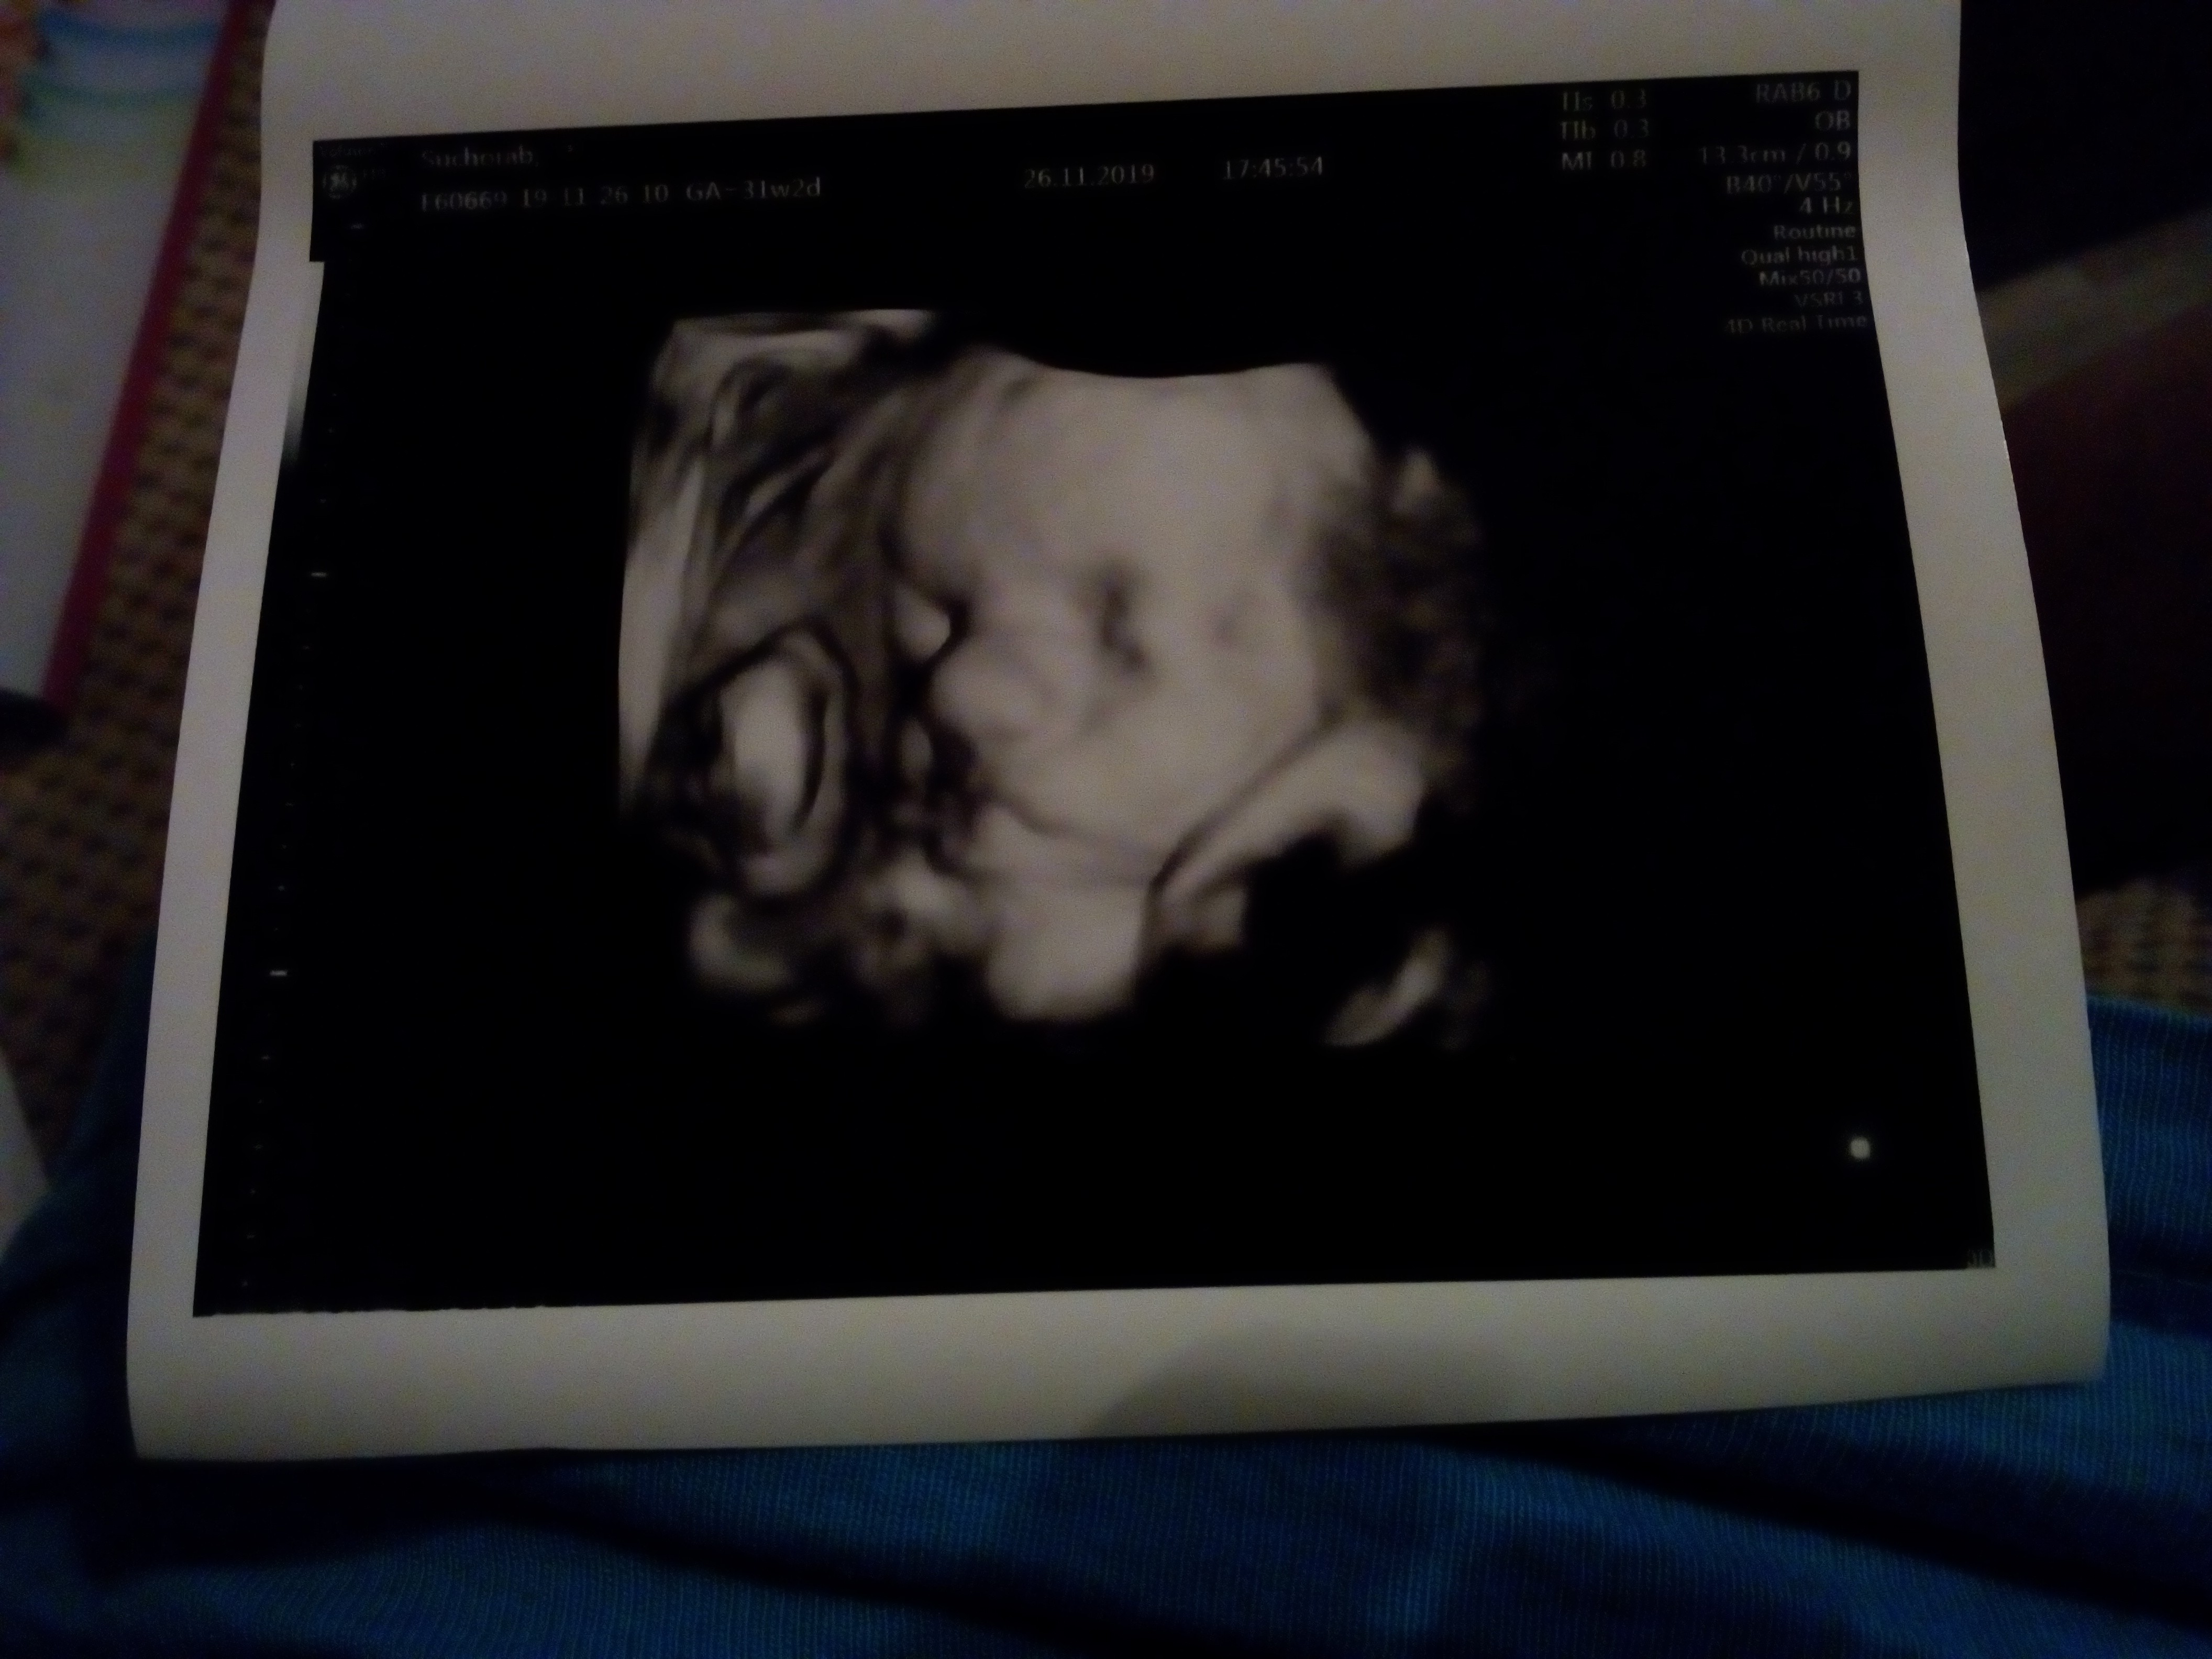

31+6. Mały ma 1850g :) dziś nie bardzo chciał pozować do zdjęć. Zasłaniał się ręką a później dodał do tego stopę ;) dr próbowała rozbujać brzuch żeby się ruszył i nagle na 3d było widać grymas. Normalnie mały, wściekły czlowieczek którego ze snu chcieli wyrwać ;)

Dziewczyny ja też dziś po wizycie Zobacz załącznik 104991331+6. Mały ma 1850g :) dziś nie bardzo chciał pozować do zdjęć. Zasłaniał się ręką a później dodał do tego stopę ;) dr próbowała rozbujać brzuch żeby się ruszył i nagle na 3d było widać grymas. Normalnie mały, wściekły czlowieczek którego ze snu chcieli wyrwać ;)Zobacz załącznik 1049914